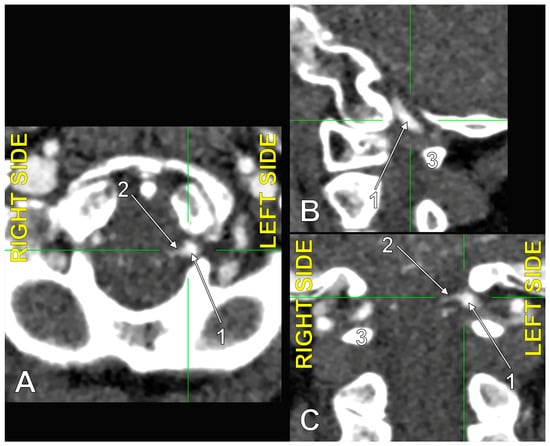

4.3. Extradural Origin of the PICA

4.4. Transdural Origin of the PICA